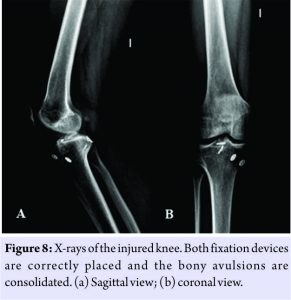

Passive mobilization of the knee started 24 h after surgery. Full weight-bearing of the limb was allowed with a knee brace in extension during the 1st 4 weeks. After the 4th week, the immobilizer was removed and progressive full knee flexion was allowed. The patient returned to his usual sports activity 6 months after the intervention. No post-operative complications appeared. At18-month follow-up, the patient was conducting normal life and free of symptoms. At clinical examination, Lachman, anterior drawer, pivotshift, posterior drawer, and reverse pivot shift tests were negative. Range of motion was 130° flexion, with a 5°lack of extension. The International Knee Documentation Committee score was 83.80 points. Lysholm scale was 85 points. Patient resumed activities of daily living without any problem. Consolidation of both tibial spine avulsions was confirmed by anteroposterior and lateral X-ray (Fig. 8) and by magnetic resonance imaging.